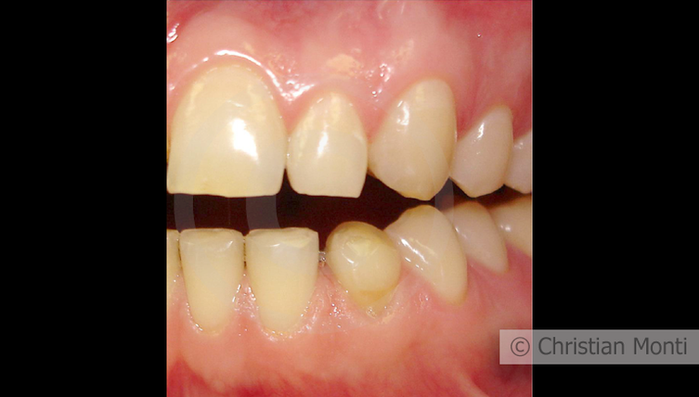

EDENTULIA SINGOLA

Impianto in sostituzione di un canino deciduo